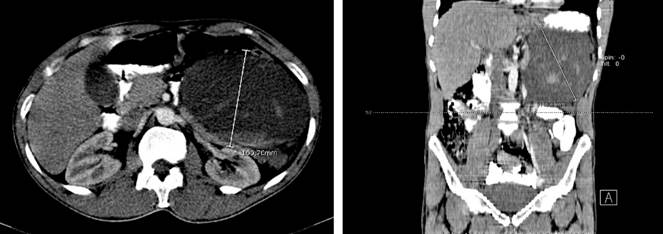

El reporte de la TAC evidenció la presencia de una voluminosa colección que se proyectaba a nivel retroperitoneal izquierdo, que desplazaba el colon y riñón ipsilateral con un contenido heterogéneo y áreas hiperdensas en su interior, formando un nivel, lo que sugirió una colección con diferentes estadios evolutivos de sangrado, en sus mayores diámetros con medidas cerca de 154 x 135 x 100 mm para un volumen aproximado 180 mL. Las lesiones ejercieron un efecto de masa igualmente en el cuerpo del páncreas y se proyectó hacia la transcavidad de los epiplones. Luego de la administración de contraste, no se observaron áreas de realce por esta lesión; se observó el páncreas de aspecto delgado a nivel del cuerpo y la cola por el efecto compresivo ejercido por la masa previamente descrita, asas intestinales normales, riñones y sistema excretor normal (Figuras 1 y 2).

Fue valorado por el servicio de cirugía general, en el que solicitaron marcadores tumorales (Tabla 1) para descartar una lesión neoplásica de páncreas y resonancia magnética para definir el plan quirúrgico, cuyo reporte evidenció una lesión multiseptada del cuerpo y cola del páncreas de 130 x 87 mm irregular con extensión al bazo, que no tiene plano de clivaje, y estómago fue desplazado hacia la parte superior y anterior (Figura 2); así mismo, se realizó una TAC de alta resolución de tórax como estudio de extensión, la cual fue reportada dentro de los límites normales.